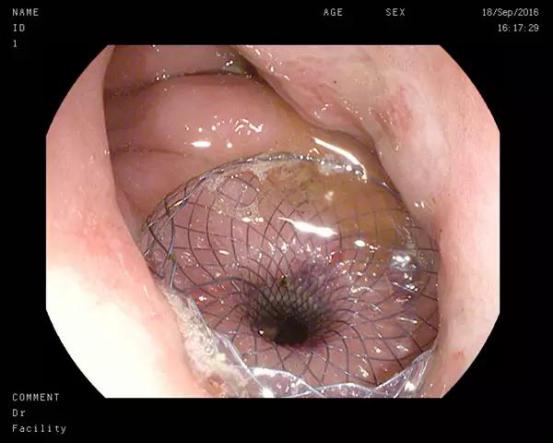

双蘑菇头支架被成功植入到胃壁和囊壁之间

我院东院内镜中心张俊勇副主任自2012年起率先开展超声内镜胰腺假性囊肿穿刺引流术,在超声内镜引导下在胃腔内植入贯穿胃壁和毗邻囊肿壁的覆膜胆道支架,将囊液引流至胃腔最终由肠道自然排出,至今已成功完成数十例。该技术既避免了传统体表穿刺的“引流盲区”,又避免了患者体外长期带管的不便以及外科手术的巨大创伤,有效改善了胰腺假性囊肿的传统治疗方法。但由于囊肿内囊液经引流后囊壁产生弹性回缩以及胃壁蠕动,且支架表面光滑,极少部分患者可能出现支架滑脱进入胃腔、囊腔或腹腔,引起感染或出血,存在需要进行二次治疗的风险。

此次患者郑某、耿某均于半年前发生胰腺炎,病情稳定后逐渐出现腹胀、进食后呕吐等梗阻症状,入院后经CT检查发现巨大胰腺假性囊肿形成。我院东院消化内科以张春清主任、张俊勇副主任医师为首的超声内镜介入团队,带领冯华主治医师、王广川主治医师,结合疾病特点和既往经验,反复研究琢磨,借鉴先心病室间隔缺损“封堵器”的原理,创新采用特制双蘑菇头覆膜支架代替传统胆道支架,通过膨大的双蘑菇头将胃壁和囊壁牢牢卡在一起,从而避免支架滑脱的可能,另外宽大的蘑菇头使术者可以轻松的操作鼻胃镜经支架中间孔道进入囊腔,进而对囊内坏死物质进行冲洗和清理,促进患者恢复。两位患者在植入双蘑菇头支架后,腹胀症状迅速缓解,即可正常饮食,经4周引流,复查CT囊肿基本消失,支架无任何移位,遂在内镜下将支架取出,胃壁创口愈合良好。